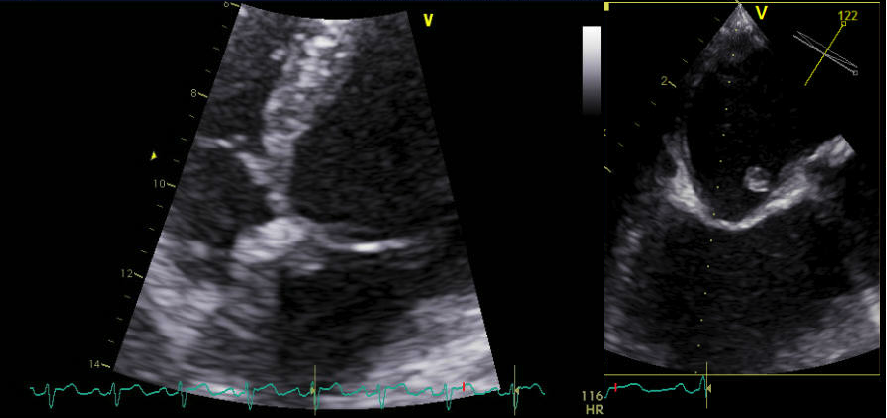

Patient was assessed with Transthoracic echocardiography (TTE) which showed mild left ventricular dysfunction (with ejection fraction of 40%) and a small mass attached to the lower interatrial septum (Figure 8). The findings were confirmed in transesophygeal echocardiography (TEE) study that described a pedunculated mass seen at the lower interatrial septum measured 0.8x0.6x0.5 cm (Figure 9 and 10) close to mitral aortic continuity. This was consistent with left atrial myxoma.

Figure 8: 2-D TTE in apical 4-chamber view and 2-D TEE showing small pedunculated myxomal mass measuring 0.8x0.6x0.5 cm attached to the lower interatrial septum on left atrial side.